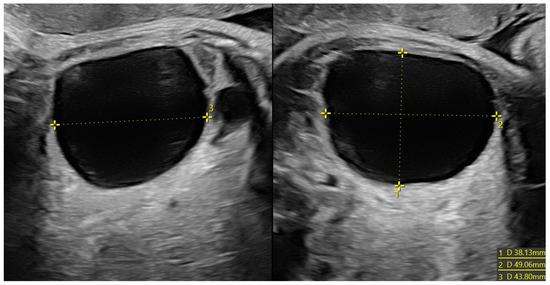

Figure 2. Voluminous ovarian cyst in a fetus at 34 weeks of gestation with anechoic content (38 × 49 × 44 mm in diameter) and no vascularization at Power Doppler. The formation was confirmed and did not regress after birth. Because of this, a cystectomy was performed, with no evidence of necrosis at the histological examination.